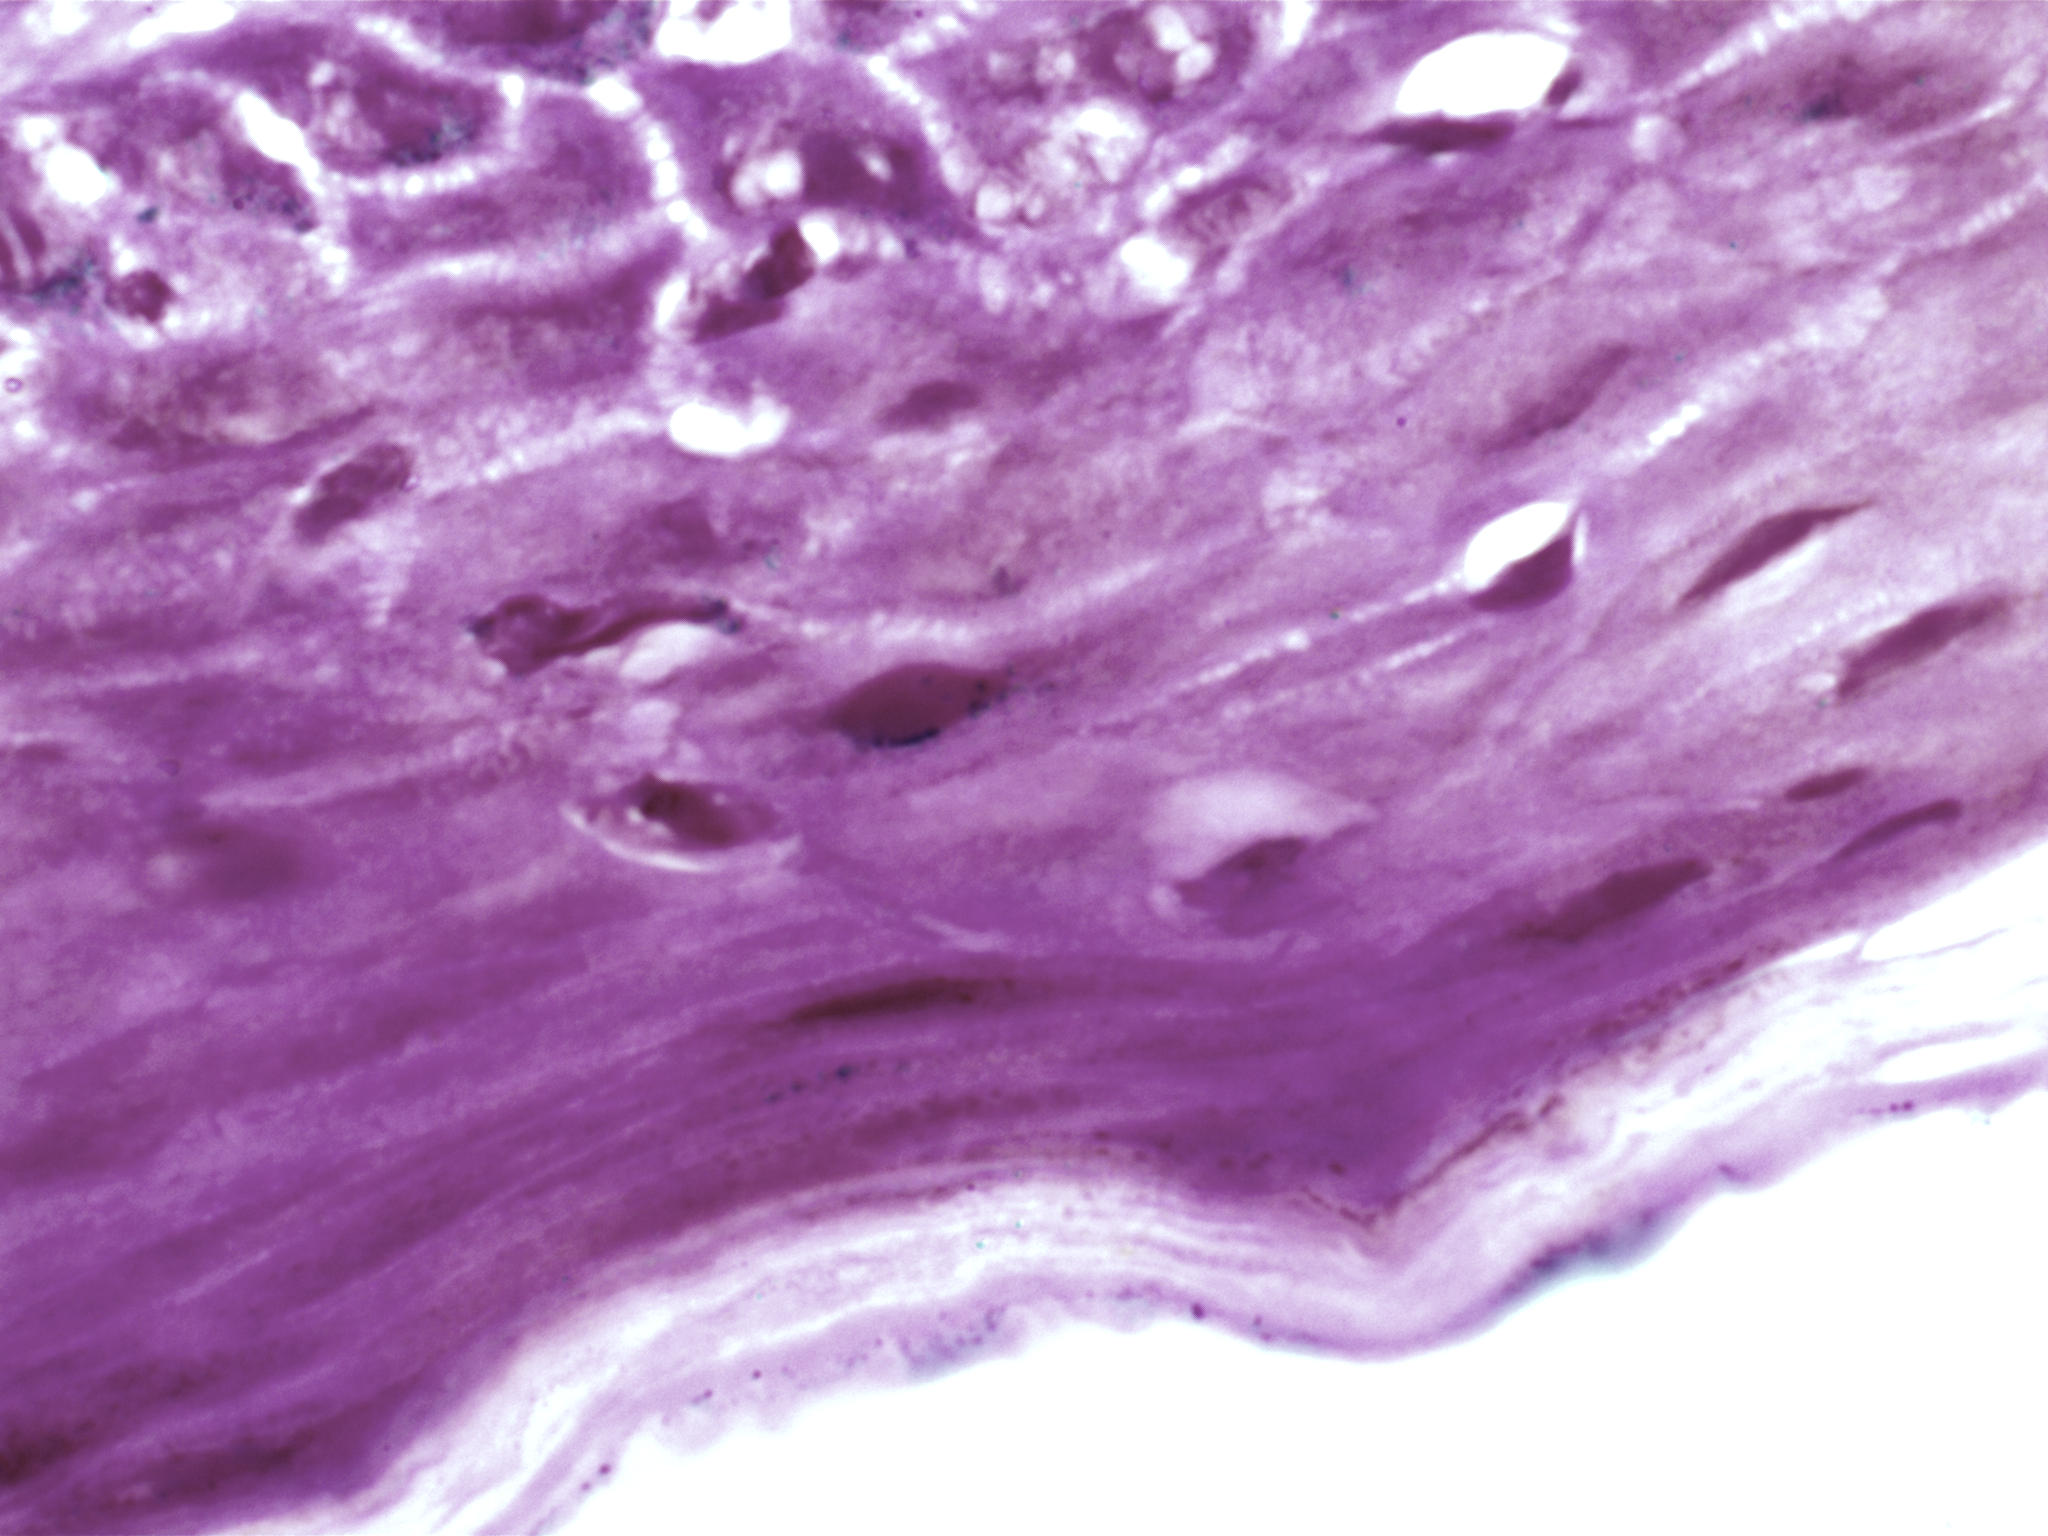

| Description: | Oral cancer is a global health challenge with a difficult histopathological diagnosis. The accurate histopathological interpretation of oral cancer tissue samples remains difficult. However, early diagnosis is very challenging due to a lack of experienced pathologists and inter- observer variability in diagnosis. The application of artificial intelligence (deep learning algorithms) for oral cancer histology images is very promising for rapid diagnosis. However, it requires a quality annotated dataset to build AI models. We present ORCHID (ORal Cancer Histology Image Database), a specialized database generated to advance research in AI-based histology image analytics of oral cancer and precancer. The ORCHID database is an extensive multicenter collection of high-resolution images captured at 1000X effective magnification (100X objective lens), encapsulating various oral cancer and precancer categories, such as oral submucous fibrosis (OSMF) and oral squamous cell carcinoma (OSCC). Additionally, it also contains grade-level sub-classifications for OSCC, such as well- differentiated (WD), moderately-differentiated (MD), and poorly-differentiated (PD). The database seeks to aid in developing innovative artificial intelligence-based rapid diagnostics for OSMF and OSCC, along with subtypes. |

| Summary: | The number of images available in each of the five classes(folders), which are as follows, Normal, OSMF, WDOSCC, MDOSCC, and PDOSCC. Each class folder consists of subfolders representing different tissue slides collected from different patients. We have made an initial attempt to provide a comprehensive image database for two of the most prominent oral conditions, OSCC and OSMF. We believe that more such databases will be made publicly available in the near future. These comprehensive image databases will facilitate the development of accurate AI-based diagnostic tools for oral diseases, ultimately improving patient care and outcomes in the field of oral healthcare. In future, integration of databases comprising molecular markers, transcriptome, metabolome, and other biomarkers, combined with oral histological image through advanced AI-driven imaging techniques, holds great promise in improving diagnostic accuracy and precision. This potential has already been observed in the diagnosis of lung and breast cancers. This expansion will aid in developing a more comprehensive AI-driven diagnostic tool. |

| The ORCHID database is an extensive multicenter collection of high-resolution images captured at 1000X effective magnification (100X objective lens). Tissue slides were collected with the approval of an ethical committee from the participating hospitals and research institutions. The buccal mucosa tissue samples were collected for three classes, normal, OSMF, and OSCC, with grade-wise annotation from the pathologists at each hospital. Biopsy samples of normal, OSMF and OSCC tissues underwent H&E staining. The staining procedure was conducted either in-house or outsourced to different laboratories. To eliminate staining variations across different laboratories, the preparation of H&E slides involved five histopathology labs, each utilizing their own independently developed and optimized protocols for the staining process. Following staining, the samples were examined under a microscope by a skilled histopathologist to assess cellular morphology, and tissue architecture, and identify any distinctive features or abnormalities specific to each sample type. This evaluation by the histopathologist involved grading the tissue slides for OSCC and OSMF, as well as differentiating between normal and diseased tissue sections. Images were acquired using a 1000X magnification (100X objective) lens from Leedz microimaging (LMI) bright field microscopy. To capture the images consistently, we utilized ToupView imaging software, which was configured for automatic adjustments. This setting applies to both white balance and camera settings, thereby standardizing the image acquisition process across different slides. The images of the H&E stained slides were captured at 1000X magnification(100X objective lens). By setting the ToupView software to automatically adjust white balance and camera settings, we aimed to minimize human intervention and the variability it introduces. This approach ensures that the images are not only consistent but also replicable in different laboratory settings, provided similar equipment and software settings are used. We collected approximately 100–150 images per tissue slide, which were stored in PNG file format. |